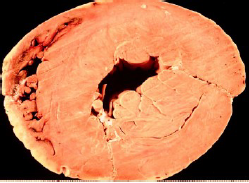

infarto transmurale;

infarto segmentale subendocardico;

microinfarti multipli;

bordo iperemico ed area ischemica giallomarrone centrale in un infarto di 5 gg;

il tessuto di granulazione rosso porpora si estende attraverso l’infarto (3-4 settimane);

la cicatrice effettiva si forma dopo circa 6 settimane dall’infarto;